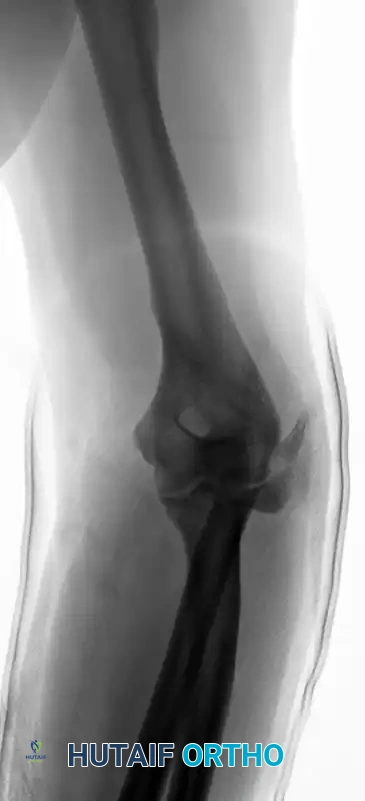

Figure 57-82C: Postoperative AP radiograph demonstrating anatomical reduction and rigid fixation with 3.5-mm compression plates.

Figure 57-82D: Postoperative lateral radiograph confirming restoration of alignment and appropriate plate contouring.